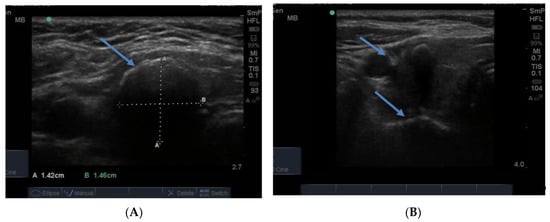

The normal gland does not contain any calcification. The presence of calcification in association with nodules generally indicates that the nodules are long standing and therefore likely to be benign. However, breaks in the wall of a calcified nodule suggest that the nodule is a cancer which has invaded into the surrounding thyroid tissue and is considered a suspicious feature of a nodule []. Calcification is sometimes seen as spots or sheets scattered throughout the thyroid. Calcification surrounding a thyroid nodule, giving it the appearance of a “bone ball”, can be felt as a hard, mobile lump on neck palpation that is crunchy on biopsy. Chronic linear or egg shell calcification is associated with shadowing because the ultrasound waves are unable to pass through calcified tissue (Figure 8A,B). Calcification is also seen in the thyroid of patients with chronic Hashimoto thyroiditis and Graves’ disease.

Figure 8.

In (A) linear calcification in the anterior aspect of a benign 15 mm nodule is seen as a curved bright hypoechoic shelf (arrow) that blocks the transmission of the ultrasound waves, so the nodule behind appears to be very hypoechoic, as in a cyst. In (B) is seen a small hypoechoic calcified nodule (upper arrow) and below it, a larger nodule with linear calcification in its anterior surface (lower arrow).